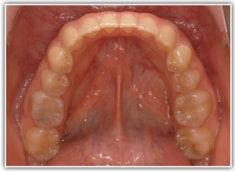

治療前